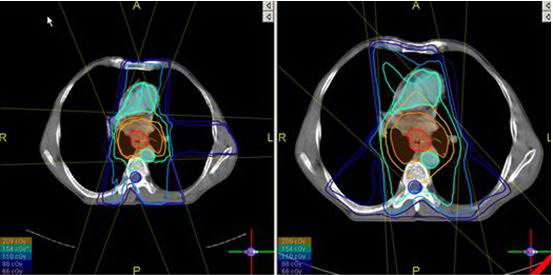

Hình

ảnh minh hoạ xạ trị điều biến liều IMRT bệnh nhân ung thư thực quản

Lập

kế hoạch xạ trị : ứng dụng phần mềm prowess-panther với thuật toán

DAO, chúng tôi sử dụng JO-IMRT với 6 trường chiếu /33 segments, phân liều

2Gy/ngày, tối ưu hóa để đạt đường đồng liều tối đa tại u là 100%, giảm

thiểu liều cho các mô lành xung quanh như tủy sống,

động mạch chủ ngực, tim chịu liều rất thấp.

Tiến hành xạ trị